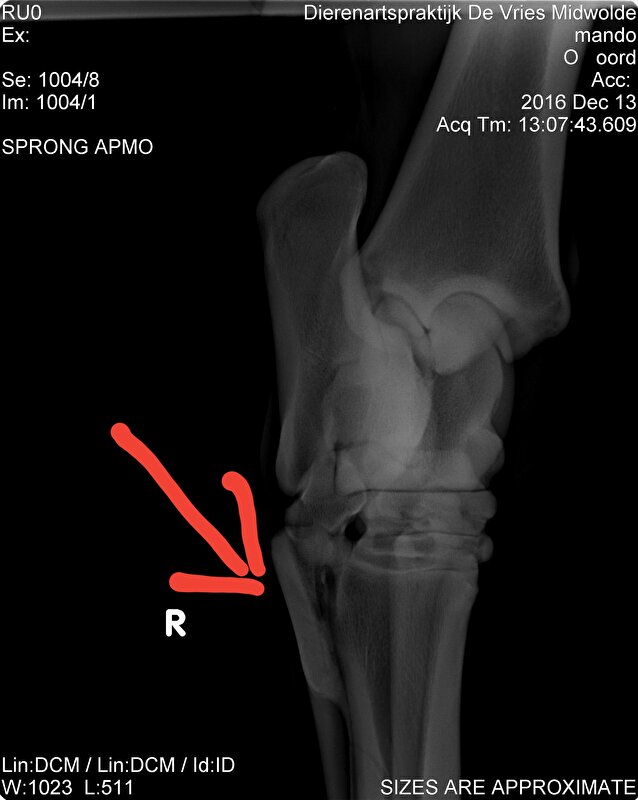

Ook had ik het gevoel dat hij soms niet lekker liep.

Niet kreupel maar ook niet rad.

December op de foto laten zetten en hij is punt gaaf op een schiefel na die hem dus soms irriteert.

Nu gewoon genieten en zien hoe hij per dag is.

Voelt het goed dan lekker trainen voelt het minder dan stapje terug.